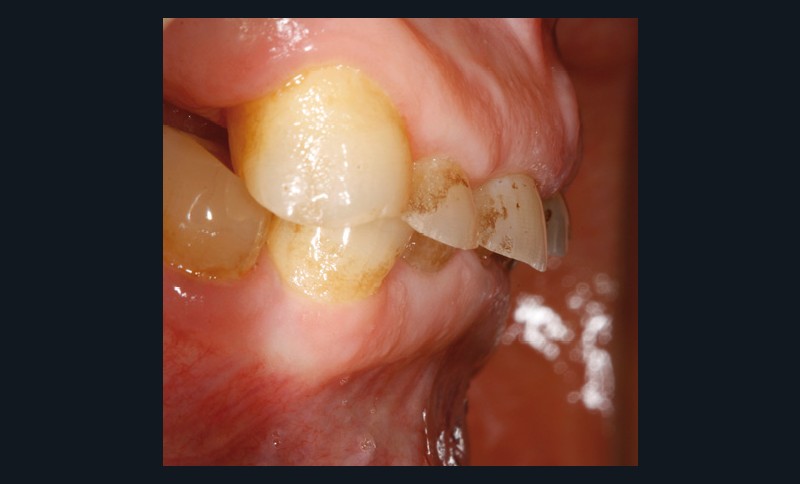

Un patient de 68 ans arrive au cabinet ; il présente de nombreux édentements ainsi qu’une usure parafonctionnelle très avancée.

Il consulte en urgence pour une douleur sur la 23 dont le traitement endodontique s’impose. Il relate également des difficultés croissantes pour s’alimenter.

Examen clinique (fig. 1-6)

• L’examen intrabuccal montre de nombreux édentements non compensés (14, 15, 16, 24, 25, 26, 27, 47 et 36) ainsi que des pertes de substance très importantes, notamment dans le secteur antérieur.

Une attrition sévère, couplée à une occlusion sans calage postérieur, a engendré des difficultés pour s’alimenter.

• Le bilan esthétique nous indique plusieurs points disgracieux :

– dysharmonie des contours gingivaux (ligne des collets) avec une ligne du sourire basse [1] ;

– perte de substance extrême du bloc incisivo-canin maxillaire et des incisives mandibulaires ;

– visibilité très limitée des dents lors d’un sourire forcé ;

– égressions compensatoires.